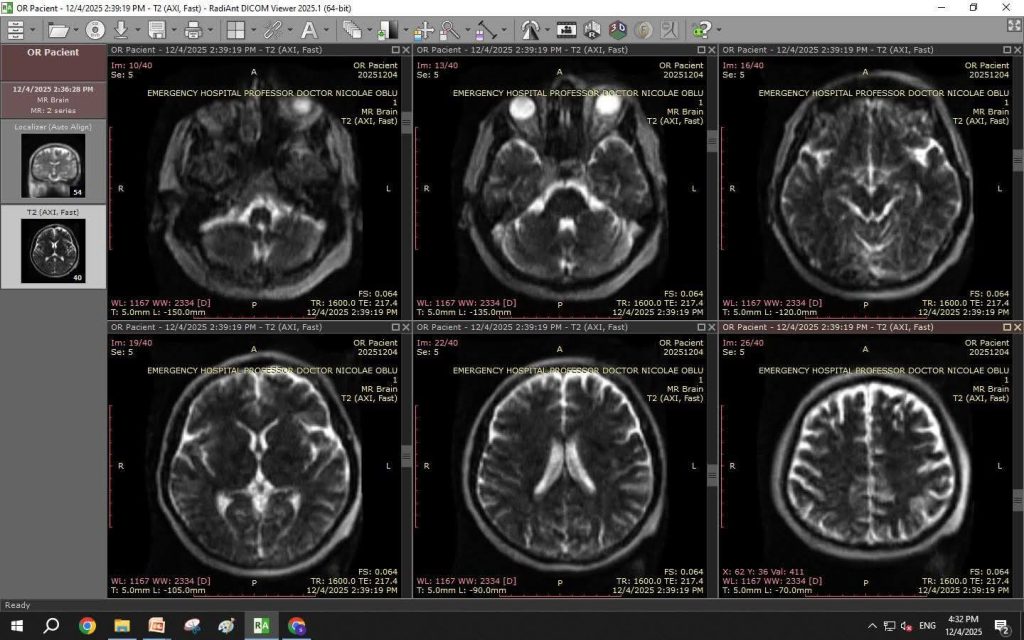

Această inovație permite efectuarea investigațiilor imagistice de înaltă performanță direct în sala de operație și în secția de terapie intensivă, eliminând nevoia deplasării pacienților critici prin spital.

Testarea sistemului a demonstrat eficiența tehnologiei: un RMN complet a fost realizat în doar 6 minute, comparativ cu aproximativ 60 de minute cât durează investigațiile clasice. Ministrul a felicitat echipa medicală și conducerea spitalului, evidențiind dedicarea personalului și viziunea managerului, Prof. univ. dr. Eva Lucian, în dezvoltarea unității medicale.